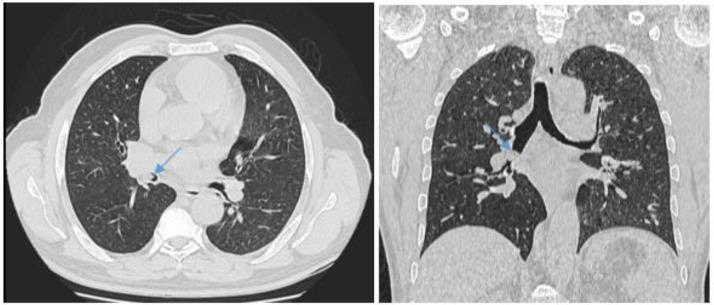

Most of the pulmonary endobronchial lesions are malignant in origin. In rare instances, benign lesions such as endobronchial hamartoma may be the cause of the endobronchial tree obstruction. We present the case of a 57-year-old male patient from North Africa who presents with a history of a 5-month cough. Imaging, particulary CT scan, showed a mass on the right intermediate bronchus whose radiological characteristics are consistent with hamartoma. A biopsy of the mass obtained via bronchoscopy revealed chronic inflammation with no evidence for malignancy. The patient was treated surgically, and anatomopathology confirmed the diagnosis of hamartoma.

https://cdn.ncbi.nlm.nih.gov/pmc/blobs/03e2/11169075/bc113e38ef85/gr1.jpg